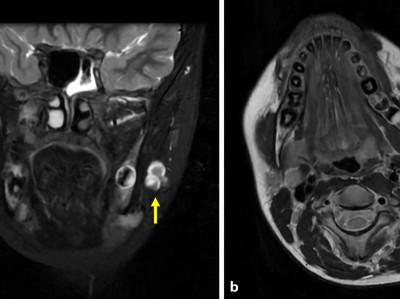

Ein Knubbel in der Wange – an welche Diagnose denken Sie?

Nach wiederholten Besuchen bei Kinder-, HNO- und Zahnärzten steht nun die 11-jährige Patientin vor Ihnen. Sie leidet seit zwei Jahren unter belastungsabhängigen Schmerzen beim Kauen. Nachdem eine vorausgegangene Sonographie und ein vergrößerter Lymphknoten eine Raumforderung im M. masseter vermuten lassen, sehen Sie nun diese MRT-Bildgebung.